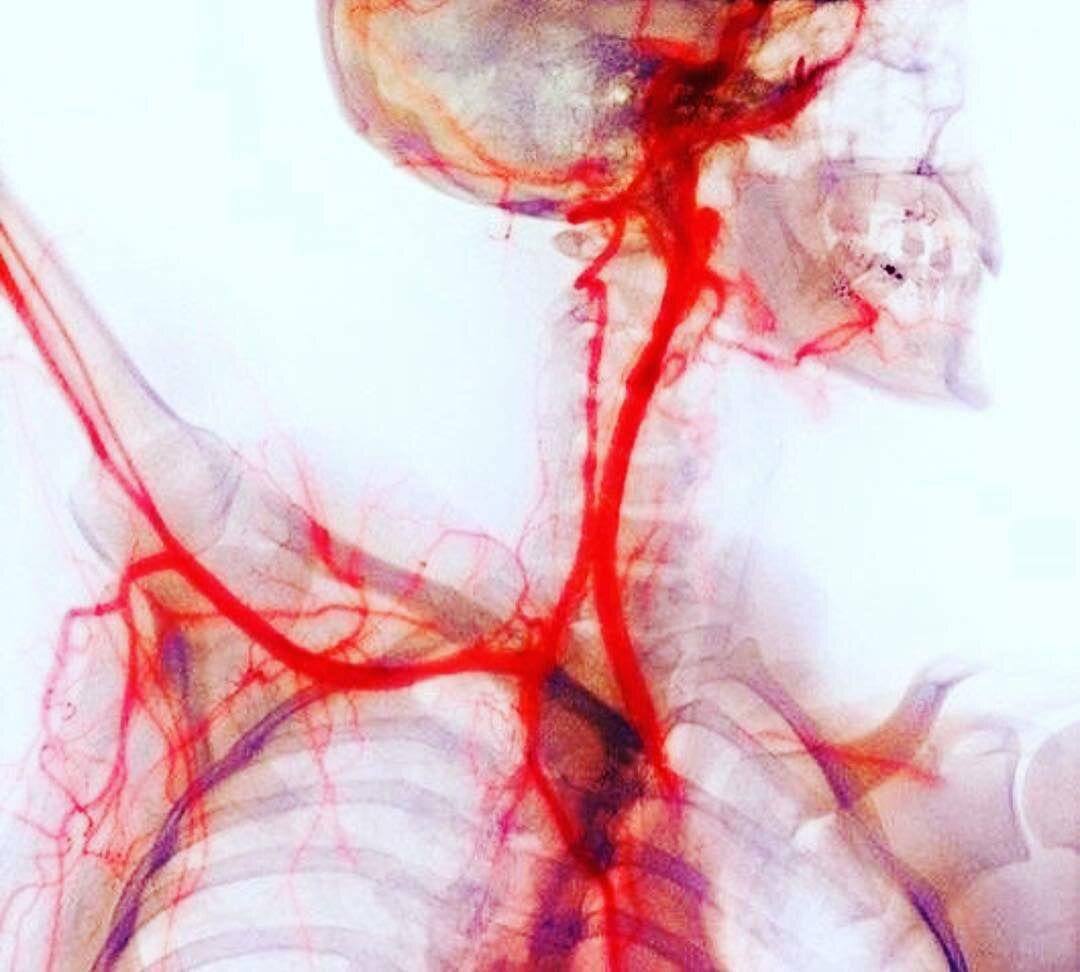

Artery 2

Artery 2 111 фотографий